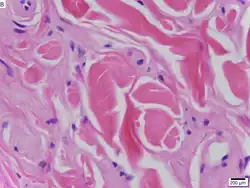

| Urbach–Wiethe disease in skin biopsy with H&E stain. | |

The dermatological symptoms are caused by a buildup of a hyaline material in the dermis and the thickening of the basement membranes in the skin.[9] The nature of this material is unknown, but researchers have suggested that it may be a glycoprotein, a glycolipid, an acid mucopolysaccharide, altered collagen or elastic tissue.[6]